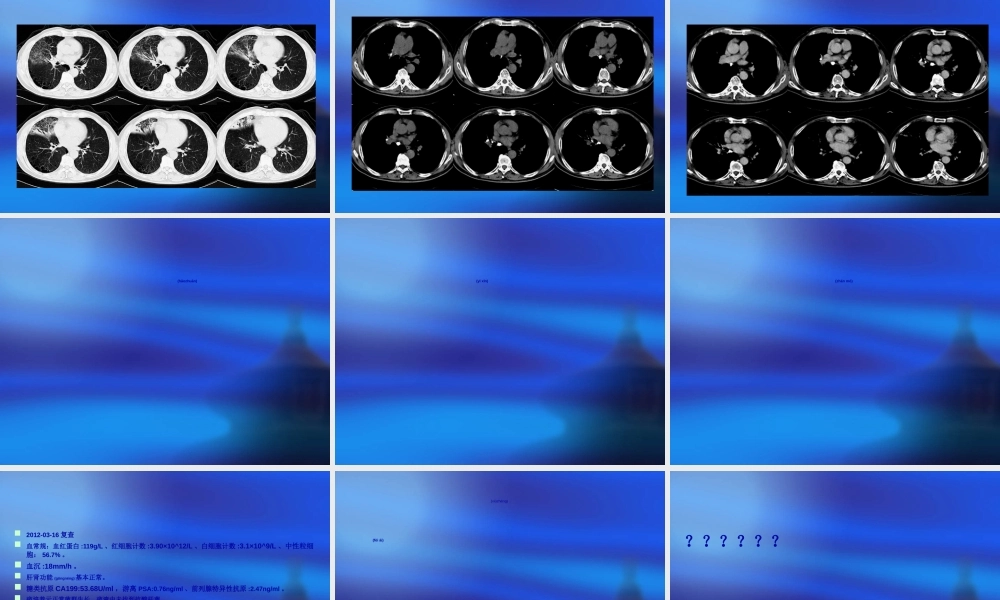

肺炎(fèiyán)?常熟市中医院呼吸科患者陈某,男性,67岁,因咳嗽咯痰二十余天于2012-02-27门诊收住入院(rùyuàn)。既往有高血压、糖尿病史三年,平时口服药物控制,血压、血糖控制不详,有前列腺增生病史,有阑尾及扁桃体手术史,有链霉素过敏史。患者2月初受寒后出现咳嗽阵作,咯吐少量黄痰,稍感畏寒,无发热,咳嗽无明显昼夜差异,无明显加重及缓解因素,无胸闷气急,开始未予重视,后患者出现咳嗽加剧(jiājù),痰量明显增加,自服头孢类抗生素(具体不详)后症状较前改善不显,故来我院就诊,为进一步诊治,门诊拟“肺炎”收入病房。患者发病以来无明显鼻塞流涕,无头痛,无咽痛咽痒,无胸闷心悸,无痰中带血,无胸痛,纳食减退,大便正常,夜尿次数多,夜眠一般。查体体温36.5℃脉搏90次/分呼吸18次/分血压120/80mmHgSaO296%(未吸氧)神志清,精神软,。全身皮肤粘膜无黄染及出血点,未及肝掌及蜘蛛痣。全身浅表淋巴结未触及肿大。口唇不绀,咽红充血,扁桃体无肿大。颈软,无抵抗感,甲状腺未触及肿大,气管居中。双侧胸廓无畸形,双肺听诊呼吸音粗,右侧中下肺可闻及较多湿性啰音。心率90次/分,律齐,各瓣膜听诊区未闻及病理性杂音。腹平软,右下腹可见陈旧性手术疤痕,全腹无压痛及反跳痛,肠鸣音约4次/分。脊柱(jǐzhù)生理弯曲存在,无叩击痛,活动度可。四肢关节活动自如,无畸形,双下肢不肿。舌红苔黄腻脉浮滑。2012-02-27本院门诊胸片提示(tíshì):右肺中叶感染,右下肺结节。胸部(xiōnɡbù)CT(2012-02-27)胸部CT平扫:右肺中叶感染(gǎnrǎn),右肺门影增大伴钙化,两肺多发肺大泡。实验室检查(jiǎnchá)2012-02-27我院门诊尿粪常规未见明显异常(yìcháng)。肝肾功能未见明显异常。血糖8.6mmol/L。血常规:WBC4.2x10^9/L,N58.6%。血Ca19961.82u/ml,CEA3.02μg/L,AFP2.37μg/L。血沉:83mm/h。纤维蛋白原:4.93g/l。C反应蛋白:7.7mg/L。细胞角蛋白片段CY211:1.42ng/ml、神经元特异性烯醇化酶:13.56ng/ml、游离PSA:1.13ng/ml、前列腺特异性抗原:5.39ng/ml。乙肝二对半、丙肝抗体阴性;艾梅抗体阴性。糖化血红蛋白:7.1%。痰培养阴性;痰找抗酸杆菌阴性。B超示:肝囊肿(nángzhǒng)、前列腺增大诊断(zhěnduàn)中医诊断:风温肺热病(rèbìnɡ)(痰热壅肺证)西医诊断:肺炎治疗(zhìliáo)治疗予“哌拉西林他唑巴坦”抗感染、“硫酸镁”解痉平喘、“氨溴索”化痰等对症处理。患者夜尿次数较多...